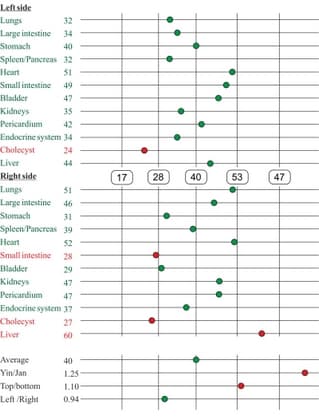

The experimental results are presented as circular charts and graphs of the total deviation from the norm. The value at the norm is equal to 0, since there is no deviation at the norm.

In the circular charts, the black line represent the initial values, and the red line represents the values while using the Aires Defender. The meridian electric potential norm is from 50 to 65 (green band).

Before application of the Aires Defender, the majority of the meridians were depressed and energy resources were sharply reduced. The neuroendocrinal, immune, and cardiovascular systems were especially depressed.

Upon examination with an Aires Defender on the projection of the celiac plexus, all electric potential measures were in the band of normal values and energy resources were restored.

The circular charts present a high degree of imbalance in the test subject’s vital body functions. Low energy resources were noted. High-risk group for serious diseases. This examination yielded an obvious example of the effect of environment on a young body.

After using the Aires Defender for 3 hours 40 minutes, a harmonization of oscillatory (wave) processes was observed and energy resources were restored, which leads to a balance in vital body functions.

The high initial value was 34. This dropped to 2 after using the Aires Defender for 3 hours 40 minutes.

The circular charts illustrate that a portion of the meridians were depressed and a portion were activated, evidence of the desynchronization of oscillatory (wave) processes which subsequently leads to the development of manifold homeostatic disorders.

After 37 minutes of the effects of the Aires Defender, most of the electric potential measures normalized. The reaction on the right was especially positive.

The value before the use of the Aires Defender was 23. After using the Aires Defender for 37 minutes, the value dropped to 8.

The following depicts the total deviation from the norm from the right (Fig. 1) and from the left (Fig. 2), under the influence of an Aires Defender.

The subject has a pronounced asymmetry in the initial measurements: 33 from the right and 44 from the left, which indicates a desynchronization of the right and left cerebral hemispheres.

After 46 hours of using the Aires Defender, the value dropped on both sides to 22 and the asymmetry was gone. After 98 hours of using the Aires Defender, the value dropped to a minimum of 5 on both sides.

Assessment of the effect of the Aires Defender using Nakatani functional diagnostics.

The results are presented as diagnostic charts and circular charts.

The diagnostic charts are interpreted as follows: The middle band is the range of normal values (green meridians). From the right is the activation band (red meridians). From the left is the depressed activity band (red meridians).

The circular charts are interpreted as follows: The blue line is the left side. The green line is the right side. The red dashed line is the generalized measurement. The normal band is green.

Diagnostic charts before application of the Aires Defender (Fig. 1) and after application for three days (Fig. 2).

These diagnostic charts show that initially energy resources are low – the average value is 28, with a norm from 25 to 55. Metabolic processes were retarded and there were signs of intoxication (Yin/Yang 1.36, with a norm of 0.9-1.1). There was a pronounced psychological and emotional load (top/bottom 1.44, with a norm of 0.8-1.2). Metabolic processes in the tissues of the locomotive mechanism were disrupted (left/right 0.88, with a norm of 0.9-1.2).

The charts is asymmetric due to the depression of some meridians and the activation of others, which indicates an imbalance of the oscillatory (wave) processes in the body. The test subject is in a high-risk group for developing serious diseases.

Under the influence of the Aires Defender, the level of functional activity was raised significantly, energy resources grew from 28 to 40, intoxication decreased, and the psychological and emotional state normalized.

The potential of most of the meridians were established in the range of normal values.

Test subject’s circular charts before the Aires Defender (Fig. 3) and after the Aires Defender (Fig. 4):

The blue line is the left side. The green line is the right side. The red dashed line is the generalized measurement.

Before using the Aires Defender, a pronounced asymmetry of the circular charts was observed due to the depression of some meridians and the activation of others.

After the effect, the chart’s asymmetry was substantially reduced and the majority of the measures were in the normal range (green band).

The test subject’s diagnostic chart at the beginning of the workday before the use of the Aires Defender (Fig. 1) and after 6 hours of working at a computer monitor with the Aires Defender (Fig. 2).

Before using the Aires Defender, the average energy resources were 32, with a norm from 25 to 55. The removal of metabolic toxins was retarded (Yin/Yang 1.31, with a norm of 0.9-1.1). Metabolic processes in the tissues of the locomotive mechanism were disrupted (Left/Right 0.74, with a norm of 0.9-1.2). The endocrine system was in a dysfunctional state.

At the end of a working day under the protection of an Aires Defender, energy resources did not fall, but rather increased from 32 to 39. Measurements for most of the meridians normalized, indicating an increase in the functional level despite the subject working for 6 hours at a computer monitor.

The test subject’s circular charts at the beginning of the workday (before application of the Aires Defender) (Fig. 3) and after working for 6 hours with the Aires Defender (Fig. 4).

Before applying the Aires Defender, a moderate asymmetry of the charts was observed due to the depression of some meridians and the activation of other meridians.

After 6 hours of working under the protection of the Aires Defender, the circular chart became more symmetric and measurements for the majority of the meridians were in the normal range of values (green band).